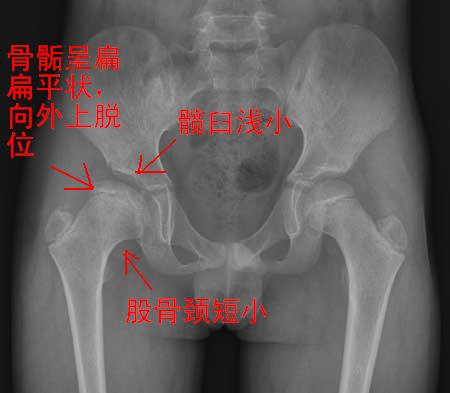

右侧先天性髋脱位

1右侧髋臼扁平,浅小

2右侧股骨头形状不规则,呈扁平状

3右股骨头向外上方脱位

4右股骨颈短小

右侧髋臼股软骨病继发髋关节半脱位,本病好发于青少年,患者感到腿痛及跛行,运动后加重。

x线表现:1、髋臼浅而宽  2、股骨头骺变扁宽及囊变,干骺端亦有相应增宽   3、由于1所述,所以股骨头可向外上方移位。关节间隙下宽上窄不对称,呈半脱位状态。4、发病早,及时治疗可恢复正常、否则会遗留髋关节半脱位及继发骨性关节炎。本例表现经典,可以诊断。